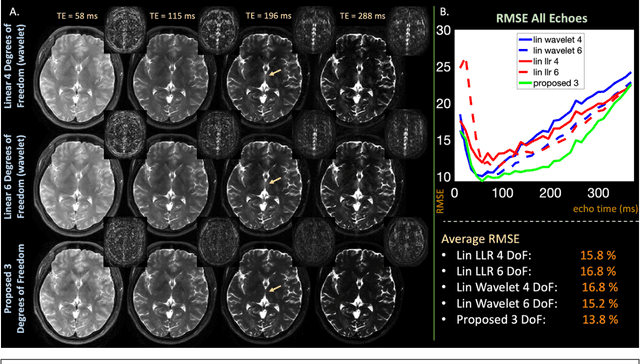

Abstract:RAKI can perform database-free MRI reconstruction by training models using only auto-calibration signal (ACS) from each specific scan. As it trains a separate model for each individual coil, learning and inference with RAKI can be computationally prohibitive, particularly for large 3D datasets. In this abstract, we accelerate RAKI more than 200 times by directly learning a coil-combined target and further improve the reconstruction performance using joint reconstruction across multiple echoes together with an elliptical-CAIPI sampling approach. We further deploy these improvements in quantitative imaging and rapidly obtain T2 and T2* parameter maps from a fast EPTI scan.